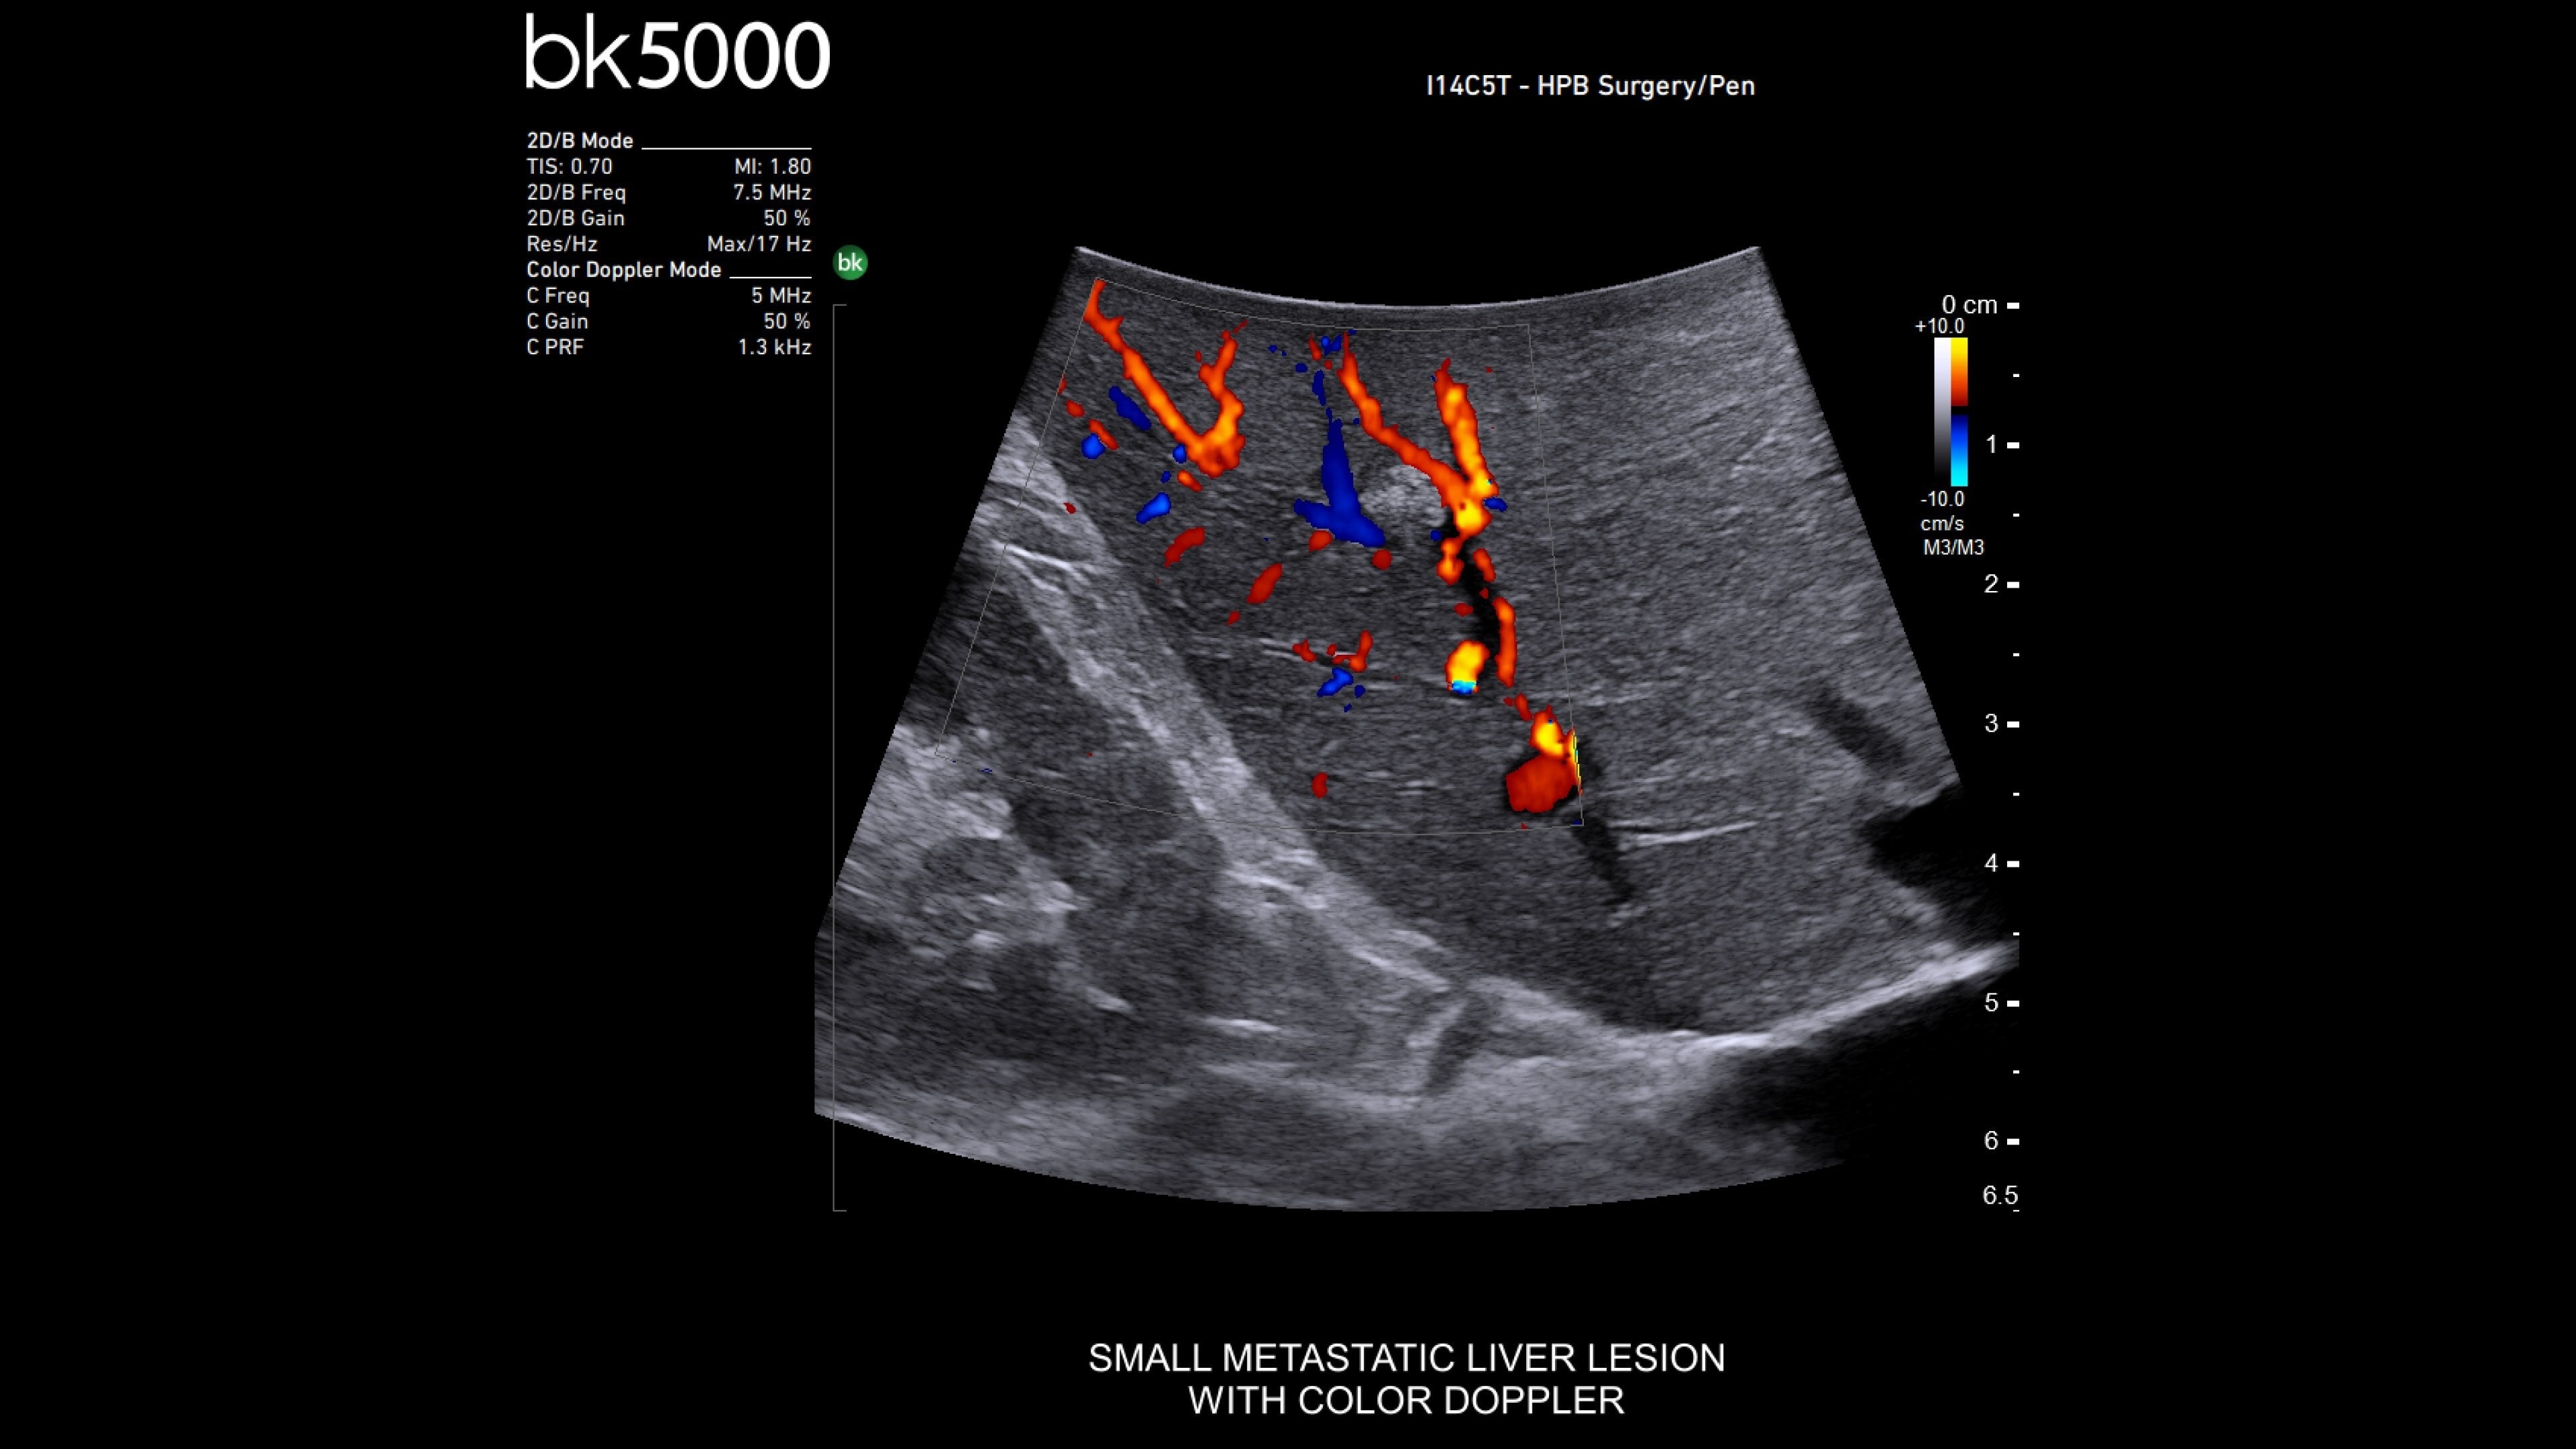

The bkActiv is a high-performance imaging system offering detailed, real-time surgical visualization. Refined through extensive research and user feedback, it supports remarkable imaging of areas of interest–neurosurgical (neuro-oncology, spine, neurovascular), urology (prostate, kidney, and bladder), hepatobiliary, colorectal, and pelvic floor.

It features technology such as Dual Live Compare for live image comparion, stored image compare, mirror image to see a live iUS image on the touch screen and sensitive color Doppler visualizes blood flow during complex surgeries.

The bkActiv ultrasound system delivers remarkable imaging for general surgery, including anorectal, robotics-assisted, and pelvic floor surgeries. Its advanced algorithms provide uniform image resolution and greater detail, while the remote control allows surgeons to adjust images within the sterile field. For anorectal surgeries, bkActiv offers high-definition imaging to visualize normal and abnormal anatomy, including anal sphincter injuries and rectal cancer. In robotics-assisted surgeries, the system's robotic transducers provide real-time, high-resolution imaging to locate and assess lesions and critical structures. For pelvic floor surgeries, bkActiv's advanced 3D architecture supports dynamic, real-time examination during procedures.